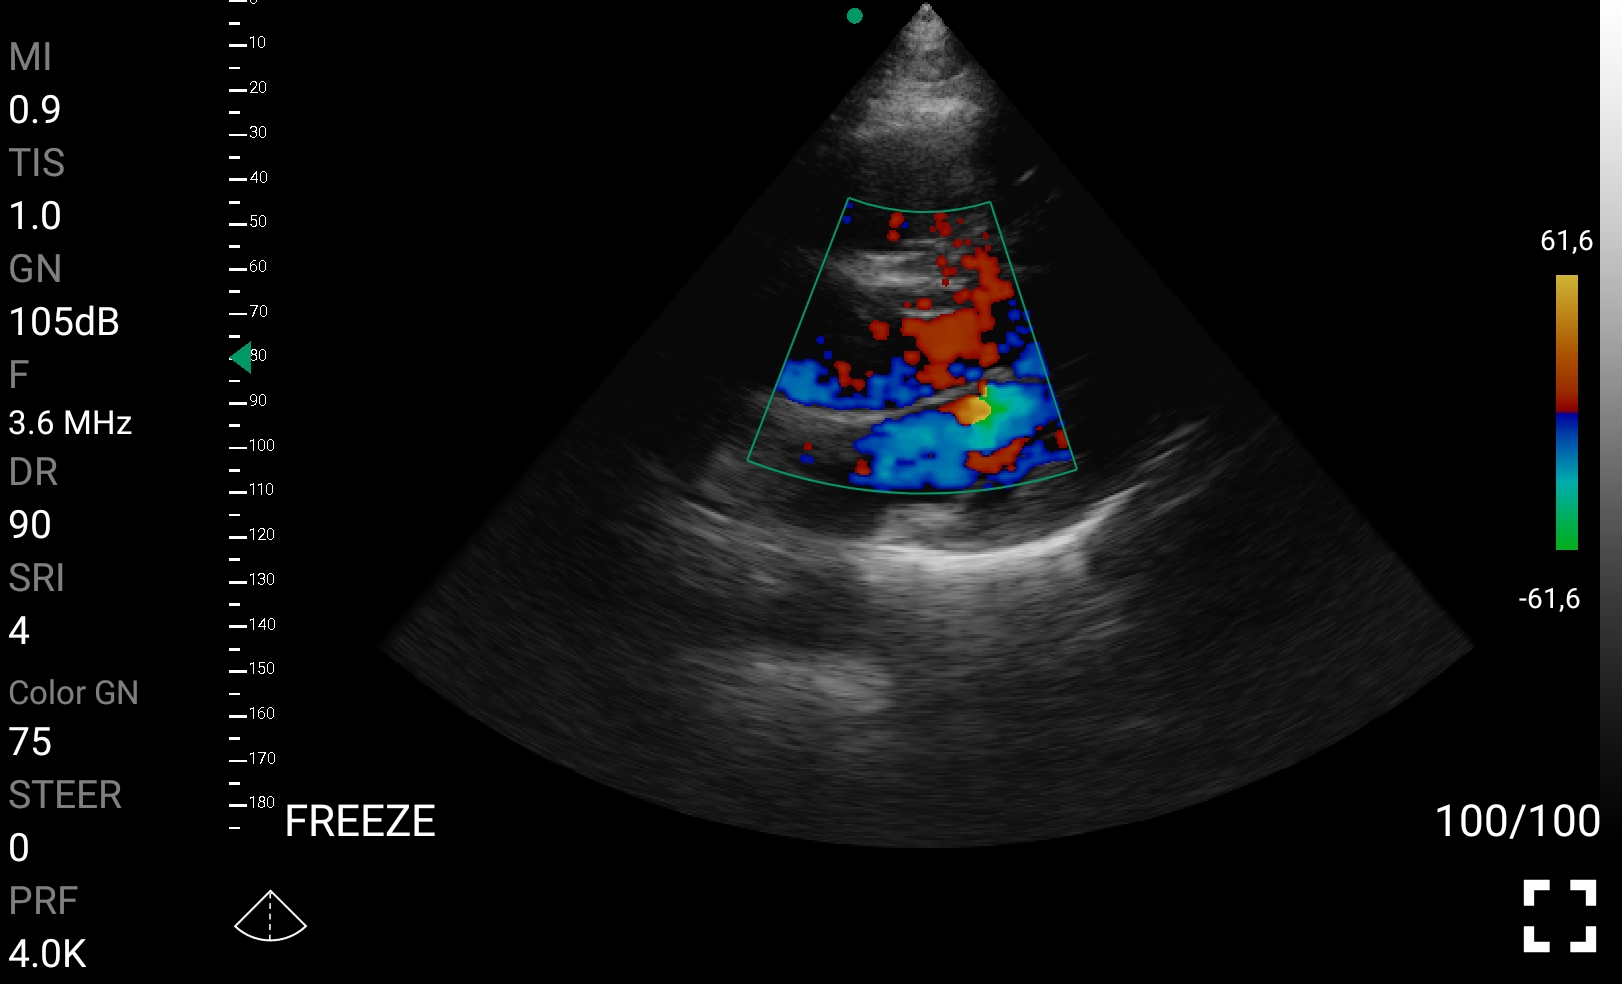

• Doppler καρδιακών βαλβίδων: Βασική εκτίμηση στένωσης/ανεπάρκειας.

Παραδείγματα

Ολες οι παραπάνω απεικονιστικές εξετάσεις έχουν ληφθεί από φορητή συσκευή όπως: Apple Iphone, Tablet, Samsung Mobile Phones και διάφορες άλλες φορητές συσκευές.

Παραδείγματα Video